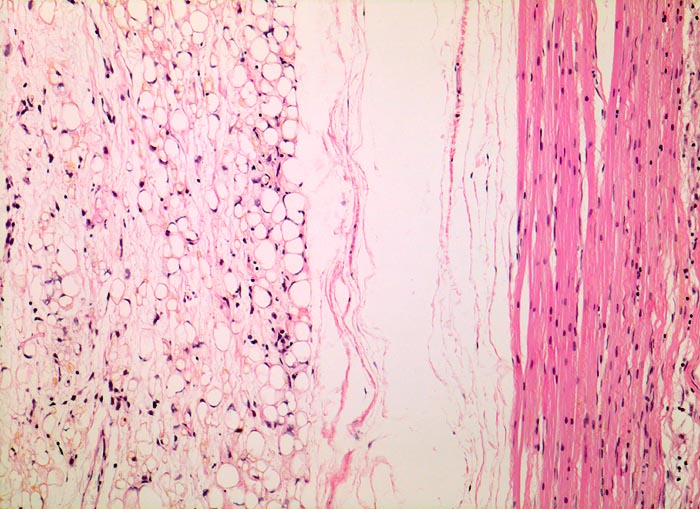

PathoPic – image database / PathoPic ID 5083 - myxoides Liposarkom

myxoides Liposarkom

maligner Tumor

Muskel, untere Extremität

Rechts im Bild komprimierte atrophe Skelettmuskulatur. Links davon die peripheren Anteile des Sarkoms mit zahlreichen Lipoblasten, die in der Übersicht an reifes Fettgewebe erinnern.

Schmerzloser Tumor am medialen Oberschenkel.

Histologie

100